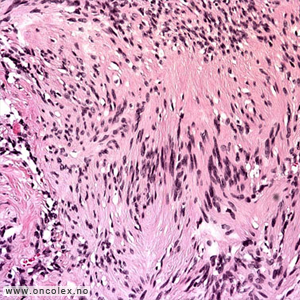

Analyse av vevsprøver

Celle- og vevsprøver sendes til cytologisk eller histologisk analyse. I tillegg til at man studerer cellene i mikroskopet gjør man avanserte immunhistokjemiske og genetiske analyser. Nøyaktig hvilke analyser som gjøres er avhengig av hva slags type svulst man mistenker at pasienten har.